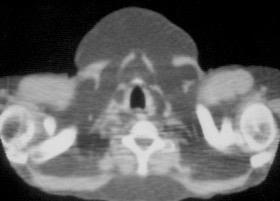

50% sin historia familiar. Manchas en “café con leche” “Pecas”. “Moluscos” cutáneos

Evolución de neurofibroma a neurofibrosarcoma. Neurofibromas (moluscos) cutáneos múltiples

Hirbe AC et al. Neurofibromatosis type 1: a multidisciplinary approach to care. Lancet Neurol 2014;.